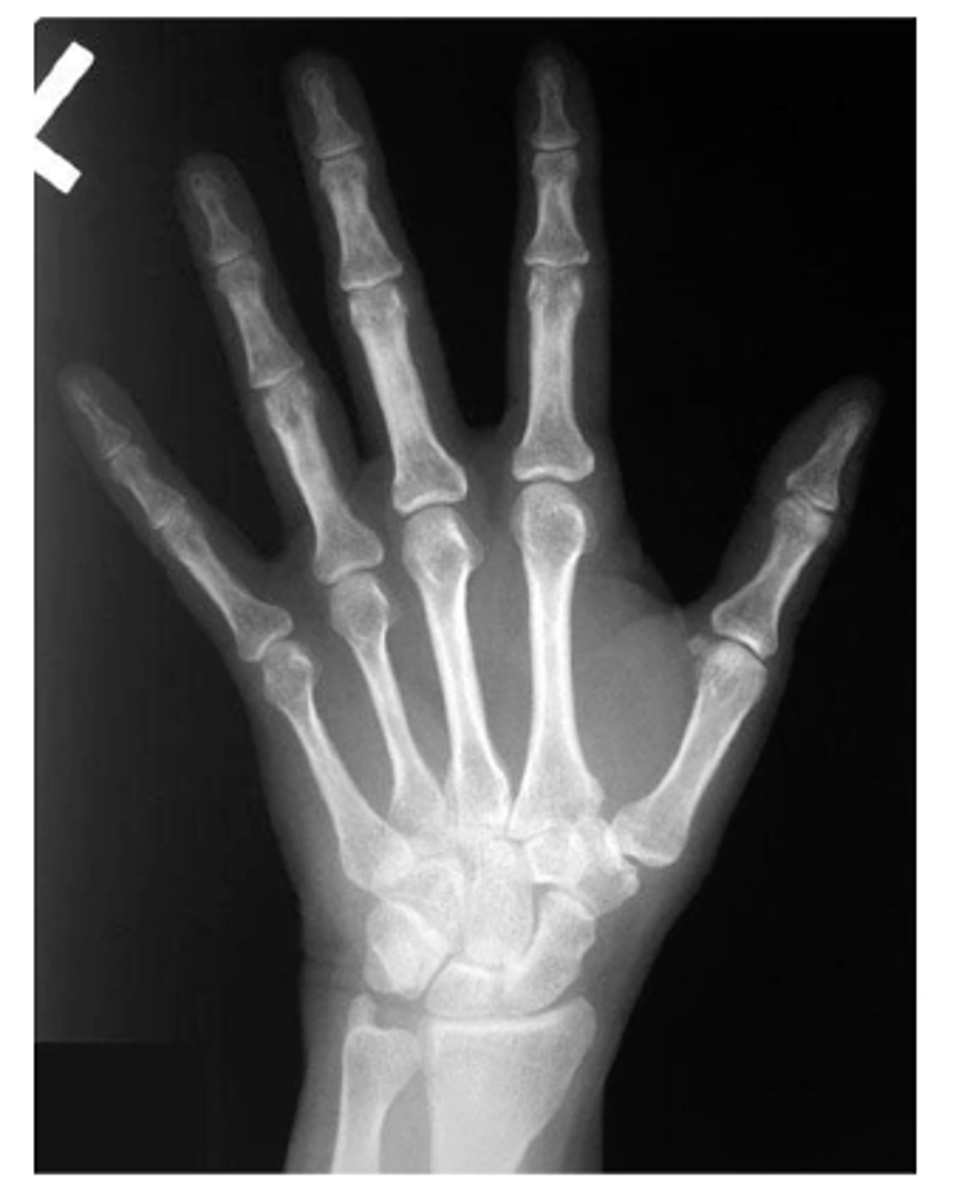

View: PA

Structure: left hand

State the type of view and structure being depicted.